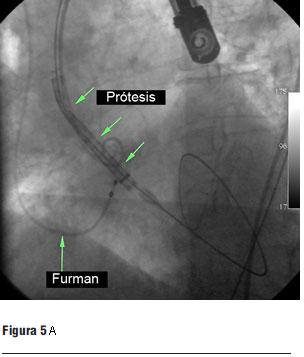

Luego de la valvuloplastia y en el menor tiempo posible se procedió al avance y posicionamiento de la válvula percutánea, con posterior liberación de la misma (figura 5 a, b, c y d).

Una vez autoexpandida se reiteraron las medidas hemodinámicas y ecocardiográficas. Comprobamos en forma inmediata la desaparición del gradiente transvalvular aórtico.

Inicialmente presentó una insuficiencia valvular periprotésica severa debido a una aposición incompleta de la válvula por la intensa calcificación. Se procedió a la postdilatación con un balón de 25 mm, lográndose una mejor coaptación de la válvula con el anillo, con disminución del grado de la insuficiencia a leve-moderada.